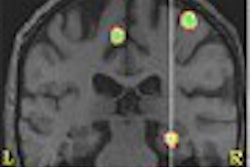

CMS said it has reviewed the scientific evidence for the radiopharmaceutical ammonia N-13 as a myocardial perfusion tracer -- in combination with FDG as the viability tracer -- in PET imaging, and has determined that it will be covered under the Medicare program.